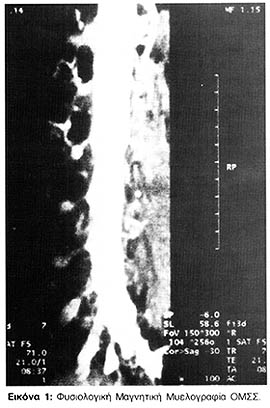

Η Μαγνητική Μυελογραφία της ΟΜΣΣ αναδεικνύει εξαιρετική σκιαγραφική αντίθεση και διακριτική ικανότητα. Οι νευρικές ρίζες διατρέχουν ωραιότατα διά μέσου του ΕΝΥ και η απεικόνιση του ΕΝΥ που εκτείνεται στα νευρικά έλυτρα είναι ικανοποιητική (Εικόνα 1). Οι εγκάρσιες τομές του νωτιαίου σάκκου δείχνουν εξαιρετικά υψηλή σκιαγραφική αντίθεση με τις περιβάλλουσες δομές και έξοχη απεικόνιση των νευρικών ριζών.

Με την κατάλληλη ακολουθία της Μαγνητικής Μυελογραφίας αναδεικνύεται καθαρά ο πληρούμενος από ΕΝΥ υπαραχνοειδής χώρος και οι νευρικές ρίζες, μπορούμε δε να εκτιμήσουμε το μέγεθος και την θέση των ριζών από την έκφυσή τους μέχρι το νωτιαίο γάγγλιο (Εικόνα 1).